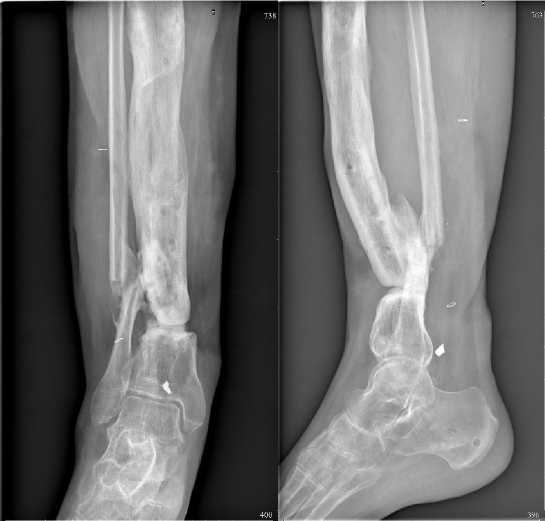

Рисунок 7. На рентгенограммах правой голени в двух проекциях определяются признаки ложного сустава правой большеберцовой кости. Консолидированный перелом нижней трети малоберцовой кости справа

Figure 7. Radiographs of the right leg in two projections show signs of a pseudoarthrosis of the right tibia. Consolidated fracture of the lower third of the fibula on the right

Рисунок 8. На рентгенограммах левой голени в двух проекциях определяются признаки хронического остеомиелита и ложного сустава дистальной трети большеберцовой кости

Figure 8. Radiographs of the left leg in two projections show signs of chronic osteomyelitis and pseudoarthrosis of the distal third of the tibia

У 10% на рентгенограммах выявлен ложный сустав (рис. 7), из них его наличие подтверждено при КТ у 6 (5,45%). Вид остеосинтеза, при котором заподозрен ложный сустав на рентгенограммах: спице-стержневой (n=2), стержневой (n=1), аппарат Иллизарова (n=2), внутрикостный (n=3), накостный (n=1), после удаления остеосинтеза (n=2).

У 2,7% раненых одномоментно выявлен остеомиелит и ложный сустав (рис. 8).